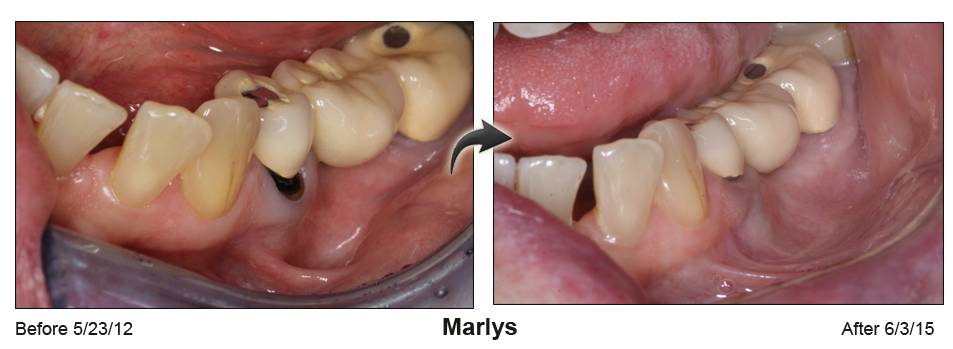

A rejuvenated smile and no sensitive roots

Gum recession not only ages your smile, it creates causes painful sensitivity to temperatures and sweets. Based in Houston & Baytown, TX, Dr. Khalid uses minimally invasive microsurgical techniques to perform cutting edge gum recession treatment and gum grafts.

Receding gums can make anyone look older

Receding gums can make anyone look older, often cause tooth sensitivity and may lead to tooth loss. Gum recession can be caused by excessive tooth brushing, gum disease or the normal aging process.

"Many people are unaware of the condition until their teeth become sensitive to cold temperatures because of root exposure. Others may be concerned by the unsightly appearance of their receding gums." says Dr. Khalid.